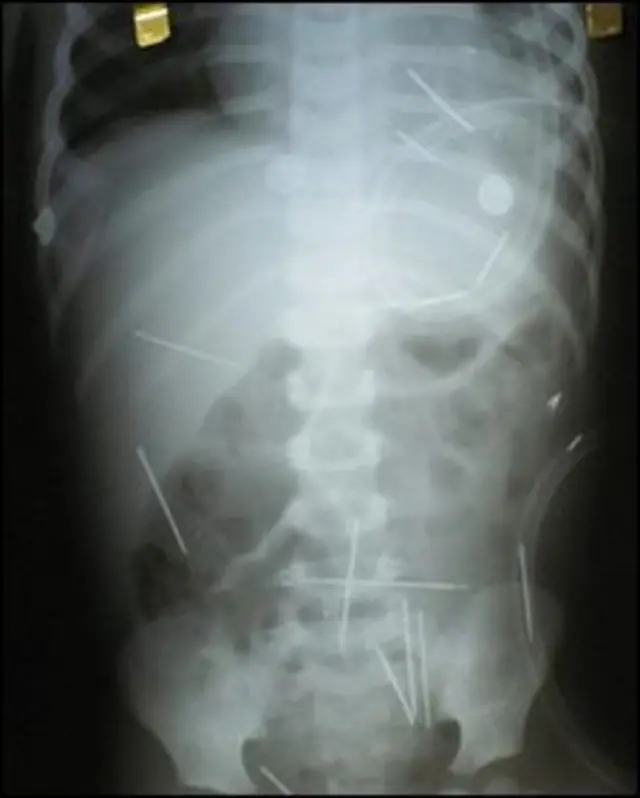

Ребенок сейчас поправляется после сделанной в пятницу хирургической операции, в ходе которой врачи изъяли из его тела четыре иглы, находившиеся в опасной близости от сердца мальчика.

Однако медики предупреждают: это далеко не последняя операция, поскольку всего с помощью рентгена удалось обнаружить около 30 игл в разных частях тела ребенка.

В ближайшее время врачи планируют операции по изъятию чужеродных предметов из его брюшной полости, кишечника и мочевого пузыря.